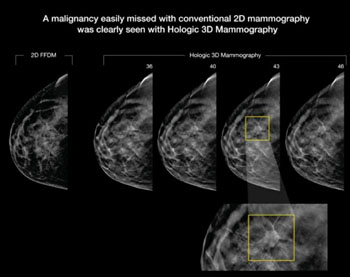

Digital Mammography Combined with Tomosynthesis Optimizes Detection of Cancer in Dense Breasts

A new study supports the effectiveness of three-dimensional mammography, which researchers found has the potential to considerably increase the rate of identifying cancer in women with dense breasts who are screened using the digital technology. More...22 Dec 2014